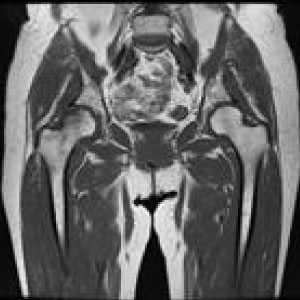

MRIはMagneticResonanceImageの略で強い磁石と電波によって人体の構造を見ることが出来る検査です。

頭部領域から脊椎・関節・骨疾患、腹部に至るまで全身部位の診断に役立ちます。

脳梗塞、脳腫瘍、脳動脈瘤、頚髄症、椎間板ヘルニア、脊柱管狭窄症、脊椎圧迫骨折、腱板損傷、各関節靭帯損傷、半月板損傷、骨壊死、肉離れ、骨腫瘍、軟部腫瘍、炎症、など